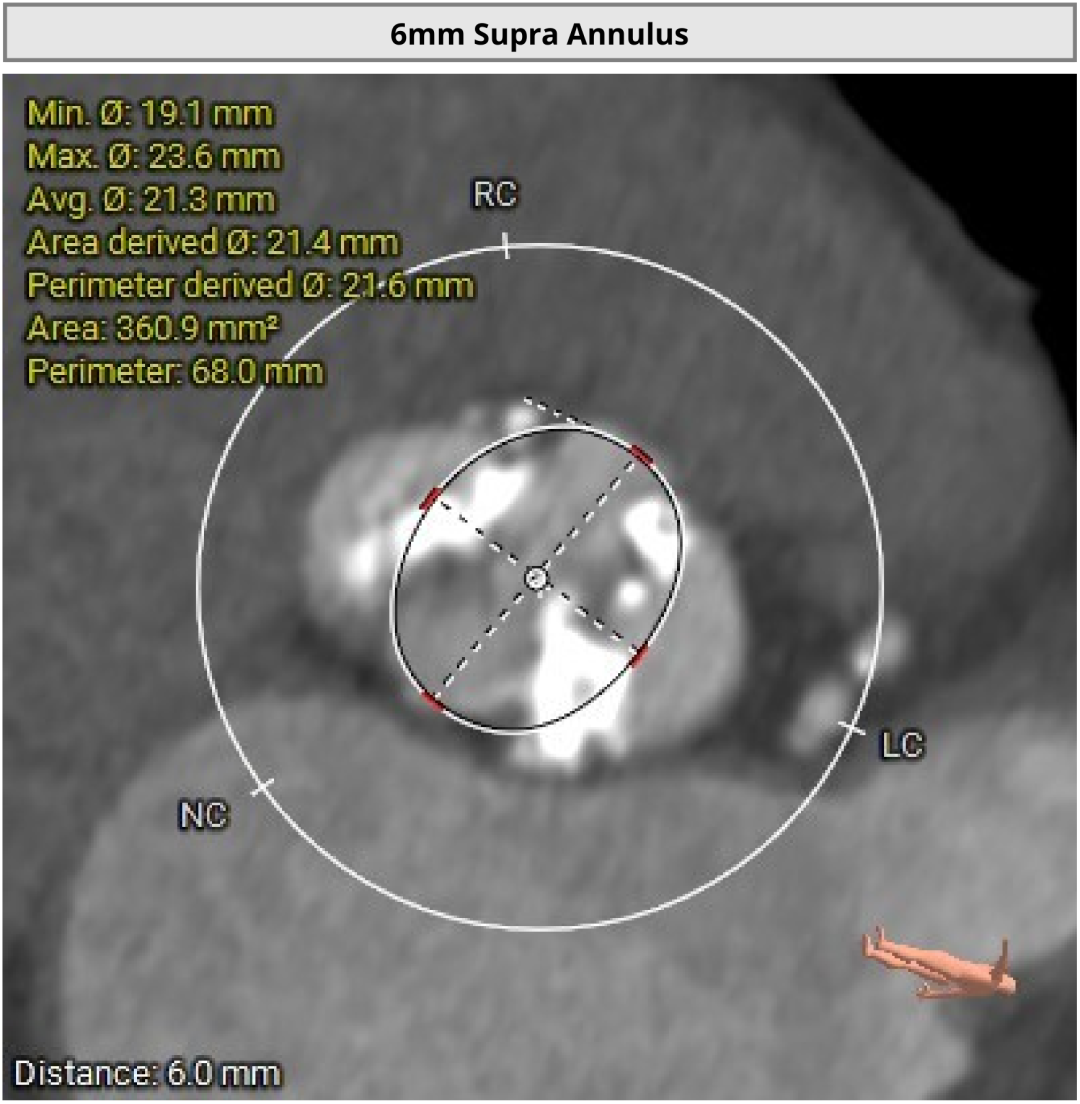

进一步评估显示,患者瓣膜狭窄程度重,瓣叶钙化明显,左心室腔径偏小,手术中对器械通过、瓣膜释放以及循环稳定性的要求都更高。团队结合术前影像和整体身体状况,制定了周密的介入治疗方案,并做好相关风险预案。

CT评估

瓣膜评估